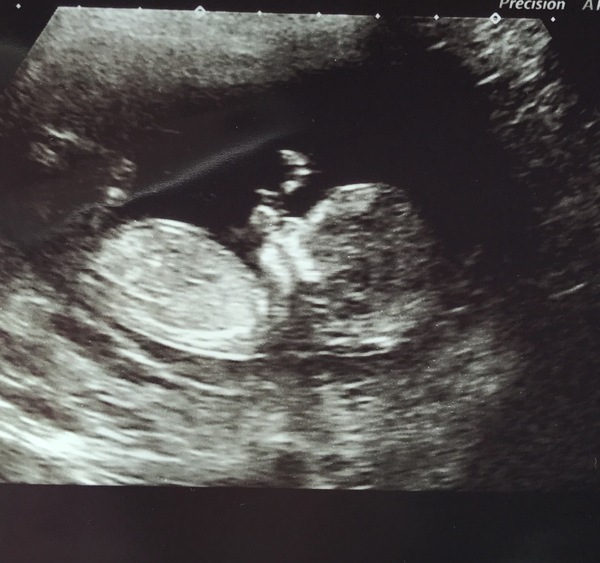

Lovely scans ladies. Good luck to everyone with scans coming up - I have one on Wednesday. Looking forward to more lovely wriggling baby pics this week!

Lovely scan pictures ladies!

Congratulations on all of the lovely scans...lovely baby-shaped babies everyone!

12 week scan all done. Looking good. Have been redated with an EDD of Christmas day (although most likely will be late November-early December still, depending on how she's doing).

Got to see her bouncing around which was lovely!

12 week scan today. Dated 12+2 so due date is now Christmas Eve. I actually was a mess at the start of the scan. The lady was lovely. I think the nt measured 1.7mm but will check my notes, have to go to mw tomorrow for bloods.

Scan went fine everything looks normal as far as she could see, feeling relieved. now edd is 20th of December but it will probably be a week or two before as it will be a section. I was enjoying my Christmas Eve due date it was an exciting talking point never mind means I will get a baby 4 days earlier so shouldn't complain.